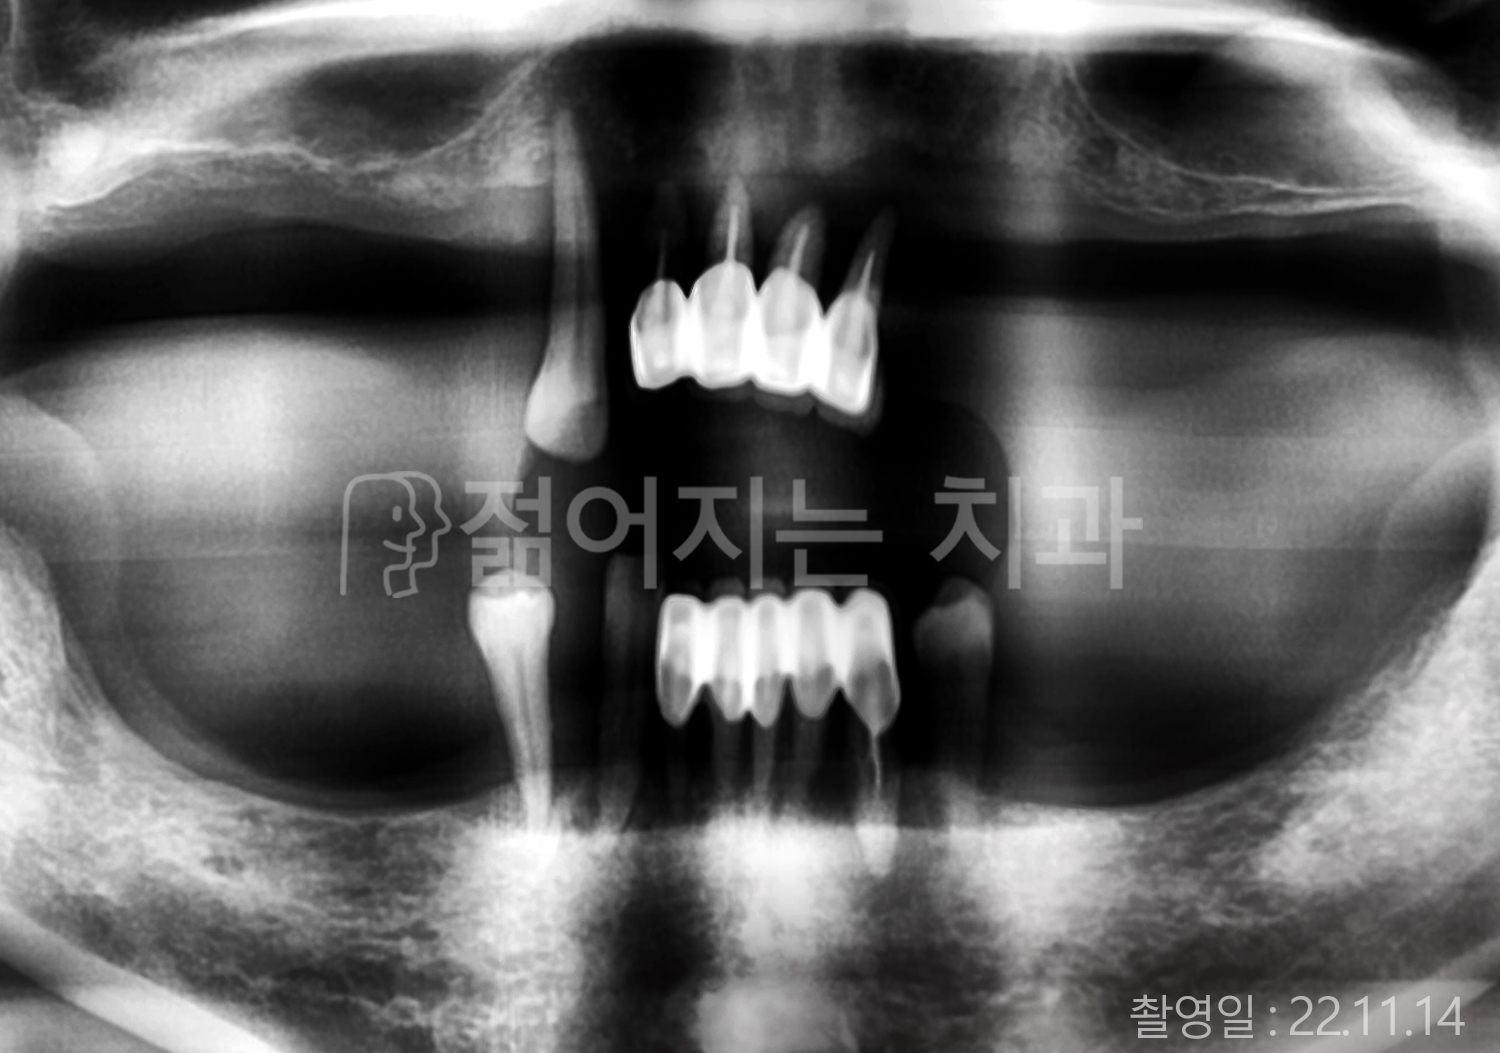

• 50대 고혈압, 당뇨, 고지혈증 전체치아 10개 이상 임플란트

• 60대 골다골증, 간경화 전체치아 10개 이상 임플란트

• 60대 고혈압, 고지혈증 전체치아 10개 이상 임플란트

• 50대 고혈압, 당뇨 전체치아 10개 이상 임플란트